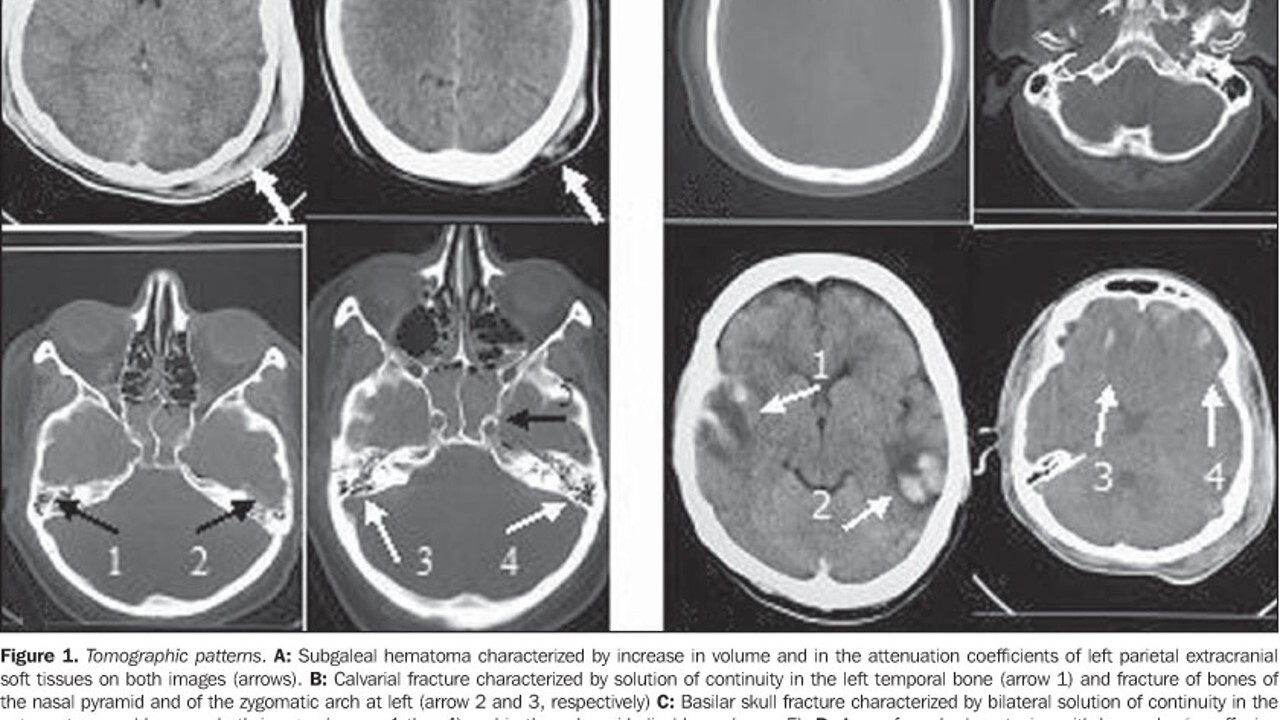

What does this image show?

Acoustic neuroma is shown in CT scan by enhancer dye injected

What do these images show?

Arterial phase (left) : abnormal course of arterial vessels to the inner ear

Venous phase (right): displacement of petrosal veins on the left